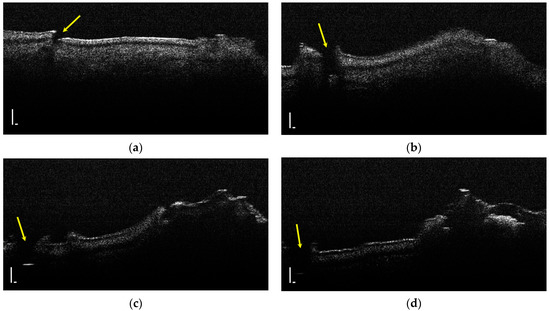

Hypoplasia represents a lack of substance and a discontinuity of the tooth enamel; thus, it was identified by the lack of an OCT signal (Figure 5).

Figure 5.

Two-dimensional OCT images of a tooth with hypoplasia (areas marked by yellow arrows): (a–d) four frames emphasizing the same hypoplasia lesion, from different perspectives (scale bar 100 μm).